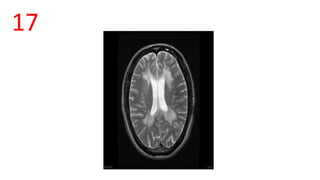

17

TIGROID SKIN/LEOPARD SKIN APPEARANCE

• Linear hypointensities radiating from ventricular margins within periventricular

white matter on T2 W images

• Seen in Metachromatic Leukodystrophy, Pelizaeus Merzbacher disease